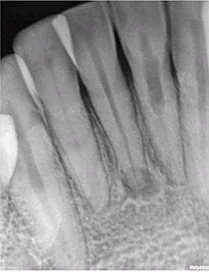

Một phụ nữ 54 tuổi với tiền sử chấn thương tới phòng khám với lý do răng 41 đau và áp xe gây khó khăn khi ăn nhai. Trên XQ 2 chiều thấy tổn thương tiêu ở răng 41 và áp xe ở răng 42 (Hình 1 và 2), rất khó để biết phạm vi nội tiêu theo hướng ngoài – trong. Tổn thương trông có vẻ rộng, nhưng có phá ra phía ngoài hay trong không? May mắn thay, phim chụp từ máy CS 8100 cho thấy nội tiêu chỉ nằm trong phạm vi ống tủy (hình 3 – 5), do đó tôi tự tin rằng điều trị tủy có thể giải quyết vấn đề của bệnh nhân, hai răng này sau đó được đặt Ca(OH)2 rồi trám bít (hình 6 và 7)

Hình 1: Phim XQ 2 chiều trước điều trị

Hình 2: XQ 2 chiều trước điều trị (ảnh chụp ở phòng khám khác